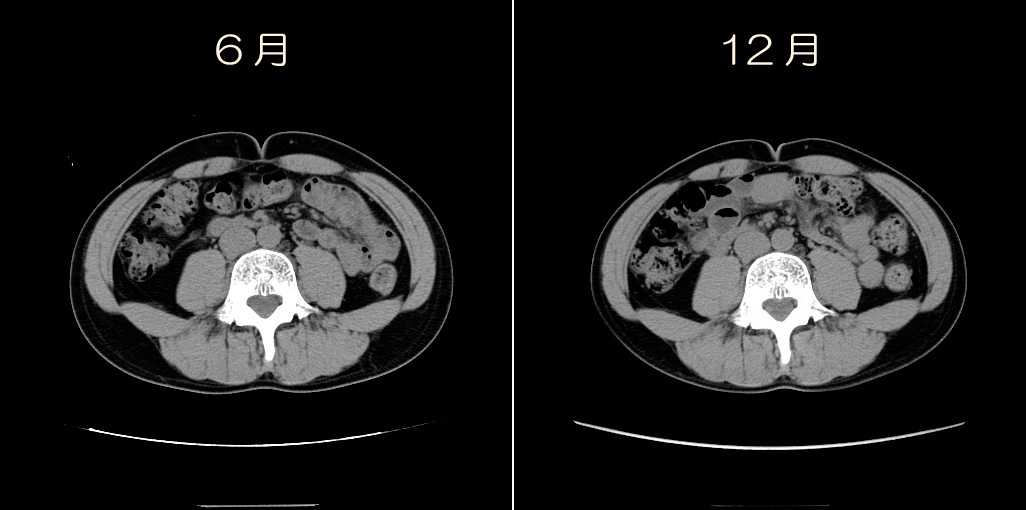

左が6月、右が今回の12月です。

わかりにくいので合成してみました。

外側の線が6月、内側の線が12月。

背中側の脂肪が多めに減ったのか!!